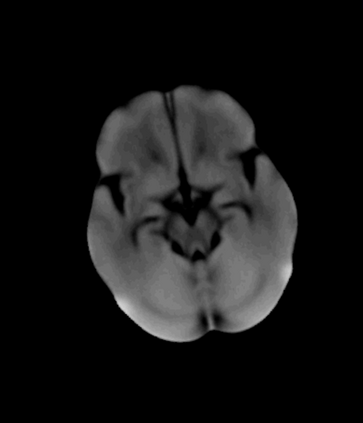

During the diagnosis of ischemic strokes, the Circle of Willis and its surrounding vessels are the arteries of interest. Their visualization in case of an acute stroke is often enabled by Computed Tomography Angiography (CTA). Still, the identification and analysis of the cerebral arteries remain time consuming in such scans due to a large number of peripheral vessels which may disturb the visual impression. In previous work we proposed VirtualDSA++, an algorithm designed to segment and label the cerebrovascular tree on CTA scans. Especially with stroke patients, labeling is a delicate procedure, as in the worst case whole hemispheres may not be present due to impeded perfusion. Hence, we extended the labeling mechanism for the cerebral arteries to identify occluded vessels. In the work at hand, we place the algorithm in a clinical context by evaluating the labeling and occlusion detection on stroke patients, where we have achieved labeling sensitivities comparable to other works between 92\,\% and 95\,\%. To the best of our knowledge, ours is the first work to address labeling and occlusion detection at once, whereby a sensitivity of 67\,\% and a specificity of 81\,\% were obtained for the latter. VirtualDSA++ also automatically segments and models the intracranial system, which we further used in a deep learning driven follow up work. We present the generic concept of iterative systematic search for pathways on all nodes of said model, which enables new interactive features. Exemplary, we derive in detail, firstly, the interactive planning of vascular interventions like the mechanical thrombectomy and secondly, the interactive suppression of vessel structures that are not of interest in diagnosing strokes (like veins). We discuss both features as well as further possibilities emerging from the proposed concept.